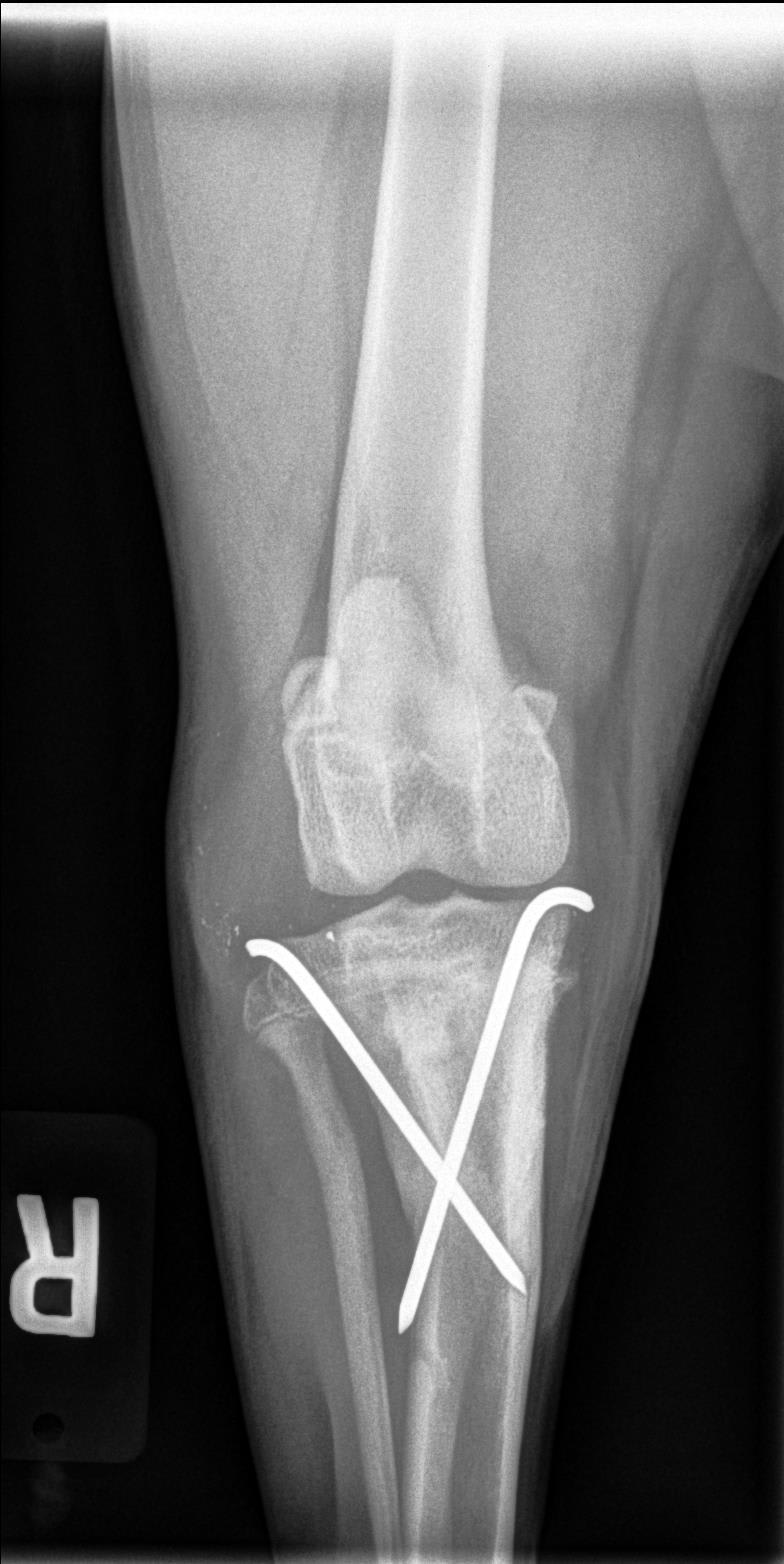

My puppy had surgery on his leg 7 weeks ago after a tibial fracture. They sent me the xrays of the healed bone and it looks like the pins are sticking all the way through the bone and coming out on the other side. The doctor said he is fine and the pins can remain in place for the rest of his life. They look sharp and I can feel a bump where they are through his skin. It looks very strange. Is this normal? The image with three pins is from 2 weeks ago before one of the pins had to be removed.

Hello and thank you for reaching out to Petco Pet Education Center, formerly Petcoach! It is normal for pins to be placed so that they stick out the other cortex (side) of the bone, as this ensures they have a good hold on the fracture fragments to prevent any movement of the fragments. As long as Toby does not develop an infection in his bone around any of the pins, and he is not exhibiting any discomfort from them, he will likely be able to have the pins in for the rest of his life. If you notice that the pins seem to be protruding more than usual, or if Toby is lame/painful on the affected leg, it is possible the pin(s) could have migrated inappropriately and/or could have become infected. This would require a visit to your veterinarian for an exam and repeat x-rays, and potentially surgery to remove the pins. I hope this helps :)